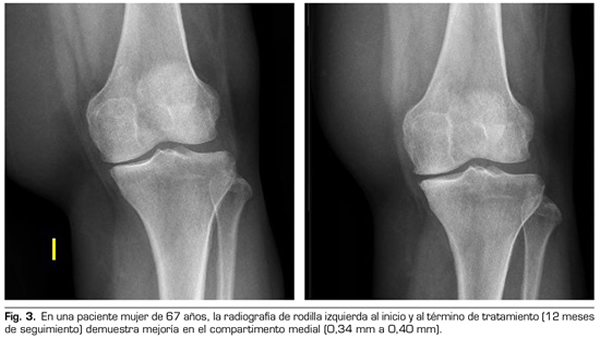

Con respecto a las variables radiológicas, al valorar a 53 de los 115 pacientes que cumplieron un año de seguimiento después del tratamiento con ozono, se observó que el compartimento interno aumento significativamente de 4,12 ± 1,41 mm a 4,4 ± 1,35 mm (p = 0,0008) y el compartimento externo aumentó de 6 ± 1,37 a 6,16 ± 1,4 mm (p = 0,0753) (Tabla II). Se presentan 2 casos clínicos como muestra del cambio radiológico en los compartimentos interno y externo (Figuras 2 y 3).

Tras un año de seguimiento con controles radio-lógicos a 53 de los 115 pacientes del estudio, el ozono (O2-O3) ha sido capaz de aumentar el mínimo espacio articular del compartimento medial (de 4,12 a 4,44 mm) y del compartimento lateral (de 6,0 a 6,16 mm), revirtiendo la artrosis de rodilla en nuestra serie de casos. Este hallazgo sugiere el efecto modificador de la enfermedad del ozono (O2-O3) sobre la artrosis de rodilla, hallazgos que coinciden con lo reportado recientemente por Fernández-Cuadros y cols. (9).